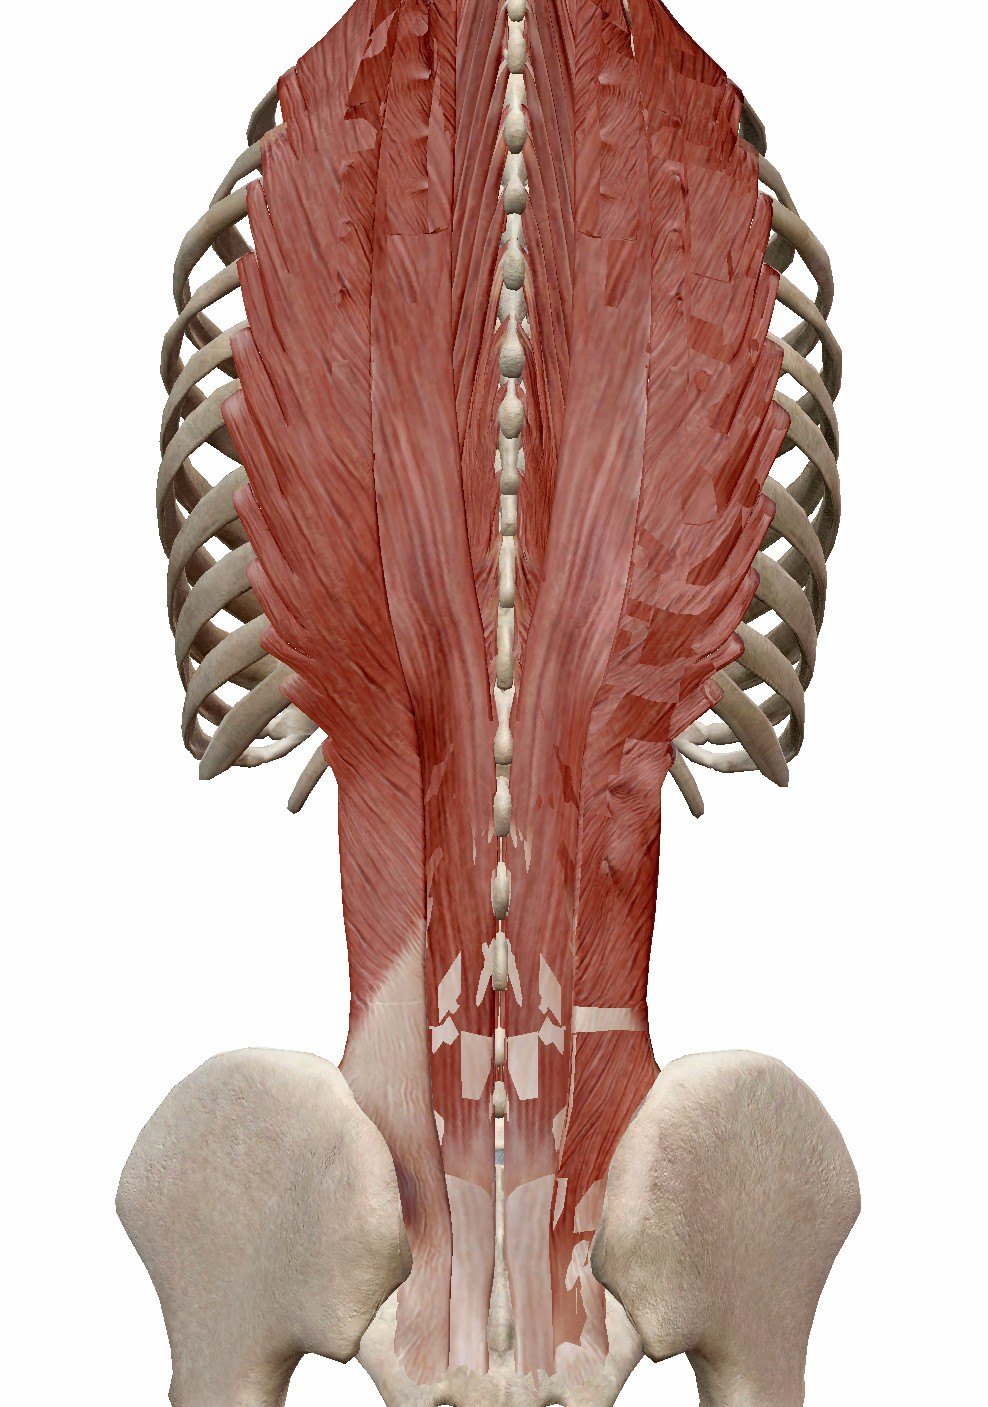

脊柱生理曲度是由腰背部的肌肉、以及腹部的肌肉所共同影响的。正常情况下是处于动态平衡的【1】。脊柱的屈伸活动,主要是由腰背部肌肉(见下图)所控制。

当我们感到腰痛的时候,腰背部脊柱椎旁肌肉肌肉会出现痉挛。这被认为是一种保护性机制,痉挛的腰背部肌肉像一个夹板一样,保护受伤的脊柱【2】。腰背部肌肉的痉挛时,失去维持脊柱生理曲度的功能,会导致腰椎生理曲度变直。